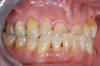

After the preparations were evaluated and accepted by the clinician, provisionals were completed with traditional crown-and-bridge techniques. Then the provisionals were fabricated with a replication stent derived from the diagnostic wax up (Figure 14). The provisionals were well-fitted to both the natural dentition and the ceramic dental implants (Figure 15). The provisional that was fixed to the implant was kept out of occlusion and had a narrow buccal-lingual occlusal table. The smaller occlusal table and short occlusal scheme provided light loading forces and stimulated the bone tissuethe brain detects the stimuli and sends osteoblasts to the area to increase bone density surrounding the implant. The recommendation for the light-loading provisional phase was to have the patient function with the provisionals for 4 weeks.

Fig 15. Provisionals 12 weeks postoperatively.

Figure 15